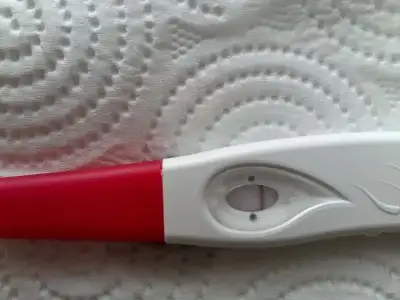

sorun değil tahmin ettim. Pazartesi için de inşallah istediğiniz sonuç olur ama olmasa da eninde sonunda olacak stres yapmamaya çalışın. bana doktor hamile kalman zor dedi, sonraki kontrolümde hamile çıktım :) yani bazen süprizleri seviyorlar

ben de hiç bi belirti yok iştah acilmasi dışında ama onu da strese bağlıyorum pek umutlu değilim

ben de hiç bi belirti yok iştah acilmasi dışında ama onu da strese bağlıyorum pek umutlu değilim